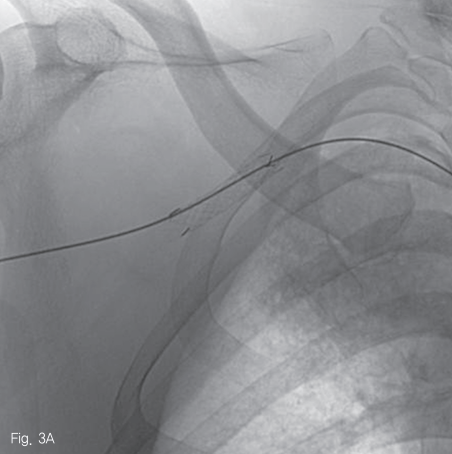

우측 대퇴동맥을 천자하여 5 Fr sheath를 거치 후, 0.035 인치 guidewire (Terumo Corp., Somerset, NJ, USA)를 이용하여 5 Fr Headhunter catheter (Cook Medical, Bloomington, IN, USA)를 팔머리동맥 근위부에 위치시킨 후 동맥 조영술을 시행하였다. 우쇄골하 동맥과 액와 동맥의 경계 부위의 위측에 조영제의 혈관외유출과 이로 인한 가성동맥류 형성을 확인하였다 (Fig. 2). 조영제 유출이 보이는 동맥의 직경은 약 6.2 mm 였으며, 거치된 카테터를 통해 Amplatz super stiff wire (Boston scientific, Natick, MA, USA)로 교체 후, 이 부위를 8 mm 직경의 4 cm 길이 자가팽창 covered 스텐트-그라프트 (vascular stent-graft, TaeWoong Medical, Gimpo, Korea)를 삽입하였다 (Fig 3A). 시술 후 우쇄골하 동맥조영술을 시행하였을 때 조영제 유출은 보이지 않았으며 (Fig. 3B), 우측 흉견봉동맥, 외측흉동맥, 견갑하동맥의 혈류가 잘 관찰되었다.

Fig 3A

A self-expandable covered stent was deployed in the distal portion of right subclavian artery, covering contrast extravasation